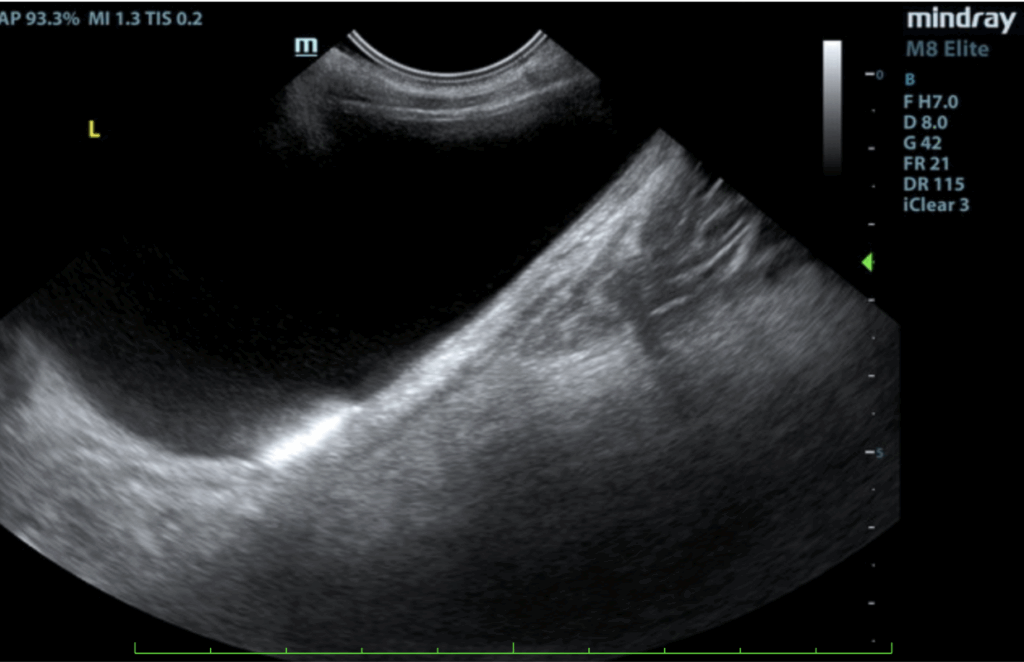

Urinary System:

The urinary bladder, trigone, and pelvic urethra presented normal thicknesses and normal tone. The ureters were not visible which is normal. Small calculi were noted, grouping of which measured 1.0 cm. No evidence of inflammatory or neoplastic changes was noted. Ureteral papillae were normal. The kidneys were both swollen and hypervascular. The left kidney measured 6.8 cm. The right kidney measured 7.59 cm.